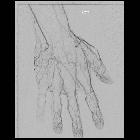

Hypothenar hammer syndrome occurs from trauma to the distal ulnar artery or proximal portion of superficial palmar arch as a result of repetitive trauma to the hypothenar eminence. Originally described in patients using hammers and screwdrivers, it is also seen in various athletes such as basketball, handball, tennis and golf players.

It may be caused by any repetitive compression or blunt trauma to this region. The ulnar artery is particularly vulnerable as it passes over the hook of hamate. Trauma to the artery may result in dissection, stenosis, occlusion or false aneurysm formation. This may be complicated by distal thromboembolism.